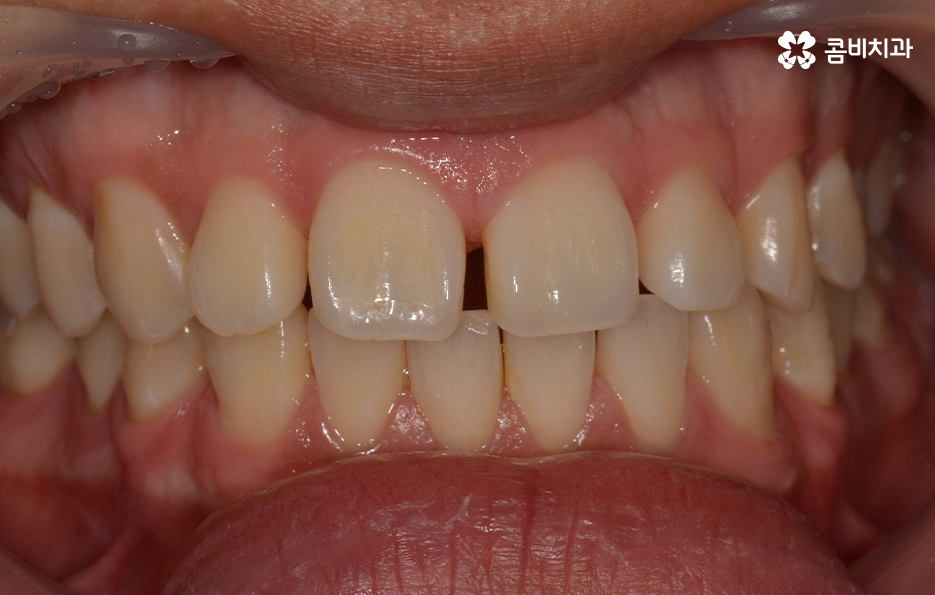

유독 앞니가 벌어져 있거나 나이가 들면서 서서히 치아가

벌어져 고민을 하시는 분들이 계신데요.

위 사례의 경우 앞니만 치아부분교정 통해서 치료가

이뤄진 사례로 치아의 돌출 여부나 골격, 교합 등을

고려하여 큰 문제 없이 치료가 가능했던 사례입니다.

위 사례의 경우 유독 앞니 위주로 치아가 벌어져 있는 상태이며

옆모습의 경우에도 비교적 양호한 상태입니다.

치아부분교정은 위 사례와 같이 대부분 앞니 6개의 치아에

부분적으로 교정 장치를 부착하여 진행이 되며

전체 교정에 비해서 저렴하고 짧은 치료 기간이 장점입니다.